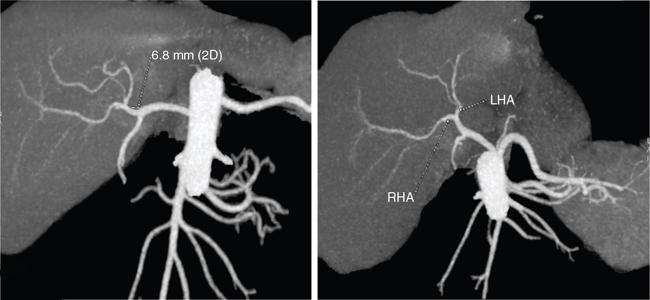

Ritu K. Kashikar, Shrinivas B. Desai Imaging is the mainstay of noninvasive diagnosis of the spectrum of abdominal pathologies or proving absence off thereof. Knowledge of normal anatomy and important normal variants is thus essential for the radiologist in order to avoid misinterpretation or erroneous diagnosis. This chapter highlights the normal anatomy of the hepatobiliary systems including the blood vessel and draining ducts and discusses relevant anatomical variants which may have important clinic implications. The liver is the largest abdominal organ, occupying the right upper abdominal quadrant and is in close approximation with the diaphragm, stomach and the gallbladder. It is largely covered by the costal cartilages. The liver is encapsulated by Glisson’s capsule which is a dense layer of connective tissue. It is covered by peritoneum, except in the regions of gallbladder fossa, fossa for inferior vena cava (IVC), and the bare area. The bare area is the posterocranial aspect of the liver, adjacent to the dorsal body wall, which is not covered by peritoneum. The liver has two surfaces, the convex diaphragmatic surface and a concave visceral surface. The slit in the hepatic hilum is called the porta hepatis and is penetrated by the right and left hepatic ducts (LHDs), hepatic artery and portal vein (PV). The distal portion of the lesser omentum is called the hepatoduodenal ligament and contains the common bile duct (CBD), hepatic artery, PV, nerves of liver and lymphatics. The liver has dual blood supply with hepatic artery providing 25% of hepatic blood and rest by portal vein (Fig. 9.2.1). Five ligaments connect the liver to the undersurface of the diaphragm. These include the falciform, the coronary and two lateral ligaments, all of which are peritoneal folds. The fifth ligament is a fibrous cord-like structure and represents the obliterated umbilical vein. The peritoneum invaginates into the liver parenchyma leading to formation of fissures. There are four normal fissures: fissures for the ligamentum teres, ligamentum venosum and gallbladder and the transverse fissure (Fig. 9.2.2). The liver is organized into microscopic functional units called lobules or acini. A central terminal hepatic venule surrounded by four to six terminal portal triads form a polygonal unit called the hepatic lobule. The terminal portal triad branches line the periphery of the unit. Between the terminal portal triads and the central hepatic venule the hepatocytes are arranged in one cell thick plates, surrounded by sinusoids. The blood flows from the terminal portal triad through sinusoids into terminal hepatic venule. Bile formed within the hepatocytes empties into terminal canaliculi which coalesce into the bile ducts (Fig. 9.2.3). This structure of the functional hepatic unit forms the basis of various functions of the liver. The normal relations of the liver are: The liver can be divided into right, left and caudate lobes. The right and left lobes are separated by the interlobular fissure and is oriented along a line passing through the gallbladder fossa inferiorly and the middle hepatic vein (MHV) superiorly (Fig. 9.2.4). This plane runs from the left of the IVC to the left of the gallbladder fossa and is a called the Cantlie’s line. Use of standardized, segmental anatomy is imperative because it facilitates communication and treatment planning. The segmental anatomy of liver is primarily based on vascular anatomy. The right lobe is divided into anterior and posterior sectors by of the right hepatic vein (RHV). The left lobe is divided into medial and lateraI sectors by an oblique plane connecting the left hepatic vein (LHV) and the falciform ligament. The liver is divided into upper and lower segments at the level of main portal vein (MPV) bifurcation (Fig. 9.2.5). Various systems are used in classification of liver anatomy. These are discussed in Table 9.2.1. The Couinaud’s system is the most commonly used and divides eight sections/segments which are discussed in details below (Table 9.2.2). 1. Segment 1 – Caudate lobe Bounded anteriorly and medially by the fissure for ligamentum venosum (Fig. 9.2.6). 2. Segment 2: Superior segment of the left lateral sector/section Bounded medially by falciform ligament and inferiorly by plane of MPV, also known as the posterior lateral sector (Bismuth, FCAT) (Fig. 9.2.7). 3. Segment 3: Inferior segment of left lateral sector/section Bounded medially by the falciform ligament and superiorly by the plane of the MPV bifurcation, also referred to as lateral anterior sector (Bismuth, FCAT) (Fig. 9.2.8). 4. Segment 4: Left medial sector/section Bounded laterally by falciform ligament and medially by Cantlie’s line (Fig. 9.2.9). 5. Segment 5: Inferior segment of the right anterior sector/section Bounded anteriorly by the gallbladder fossa and posteriorly by the plane of the RHV, superiorly bounded by the plane of MPV bifurcation (Fig. 9.2.10). 6. Segment 6: Inferior segment of the right posterior sector/section Bounded anteriorly by plane of the RHP and superiorly by the plane of the MPV bifurcation (Fig. 9.2.11). 7. Segment 7: Superior segment of the right posterior sector/section Bounded anteriorly by the plane of the RHV and inferiorly by the plane of the MPV bifurcation (Fig. 9.2.12). 8. Segment 8: Superior segment of the right anterior sector/section Bounded anteriorly by the plane of the gallbladder fossa and MHV, posteriorly bounded by the plane of the RHV and inferiorly by the plane of the MPV bifurcation (Fig. 9.2.13). Owing to its broad area of contact with the anterior abdominal wall, the liver is an ideal organ for evaluation with sonography. Ultrasound is commonly used for evaluation of size of the liver. On longitudinal scans obtained through the midhepatic line, if the liver measures 13 cm or less, it is normal in 93% of individuals (Fig. 9.2.14). The size of liver in various planes is discussed in chapter on normograms. When the area of contact between the liver and the anterior border of the right kidney, exceeds below two thirds of the kidney, the liver is considered as enlarged. The normal liver is homogeneous with fine echoes and appears evenly bright. The hepatic veins, PV and fissures interrupt the homogeneity of the liver parenchyma (Fig. 9.2.15). The parenchymal echogenicity may vary depending on the equipment, transducer and gain settings and should be judged by comparison with internal references like right renal cortex, body of the pancreas and PV walls. When compared with the adjacent normal right renal cortex the liver normally appears hyperechoic or isoechoic. The pancreas in a young individual is hypoechoic compared to the liver, and isoechoic in middle aged adults. As age progresses and fatty infiltration of the pancreas occurs, the pancreas appears hyperechoic to the liver. The liver is hypoechoic to the spleen. The normal liver reveals a density of 55–65 HU on nonenhanced scan and should appear homogenous with the exception of hypodensity in the regions of vessels and fissures. The liver parenchymal enhancement is minimal the arterial phase, with increase in density by only approximately 10 HU. This phase is usually to access vascular anatomy and to detect neovascular enhancing lesion like HCC, metastasis. Considering the fact that 75% of heptic venous supply is from the PV, the normal hepatic parenchyma shows maximum enhancement in the portal venous phase. During the venous/delayed phase the hepatic attenuation starts falling (Fig. 9.2.16). The hepatic fissures appear as linear fat containing structures. All the four fissures are well identifies on CT (Figs. 9.2.17–9.2.20). Normal liver should demonstrate uniform T1 signal similar or isointense to the paraspinal muscles and slightly hyper intense to the spleen. No signal drop should be seen on in or opposite phase. On T2W1 images liver appears slightly hyperintense to paraspinal muscles, isointense to pancreas and hypointense to spleen (Fig. 9.2.21). Following administration of extracellular contrast agents the normal liver parenchyma enhances on PV phase similar to that seen on CT. The arterial phase is preserved to determining vascular anatomy, variants and tumoural enhancement. Gadoxetic acid (Eovist) and gadobenate dimeglumine (MultiHance) are hepatobiliary agents showing excretion by the liver. In the case of gadoxetic acid, hepatic excretion is ~50%, which allows imaging in the hepatobiliary phase at ~20 minutes following injection. Gadobenate has only 3%–5% biliary excretion with hepatobiliary phase at approximately 40 minutes (Fig. 9.2.22). This property makes these agents useful in detection of nonhepatocyte containing lesions which appear hypointense to background liver on hepatobiliary phase. Hepatic anatomic variants are relatively common and represent normal interindividual variation of liver morphology. Normal Anatomic Variants Anatomic anomalies Accessory and pseudofissures may be seen in the liver. True accessory fissures result from infolding of the peritoneum usually along the undersurface of the liver and are rare. The inferior accessory fissure is the commonest accessory fissure and divides the posterior segment of the right hepatic lobe into lateral and medial portions. Diaphragmatic slips may cause indentation over the liver surface and are not commonly seen on imaging (Fig. 9.2.23). Leftward extension of the lateral segment of the left hepatic lobe appearing as a crescentic density that wraps around the spleen is referred to as sliver of liver. The left lobe of the liver may exhibit various forms: leaf like; spatular; truncated pyramid/wedge shaped; and a bifid appearance (Fig. 9.2.24). Elongated left lobe may be mimic splenomegaly, perisplenic hypoechoic collections or less commonly tumours. Imaging clues to diagnosis are establishing contiguity with liver and visualization of parenchymal vessels coursing through. The portion of the liver that extends medially from the right lobe between the IVC and fissure for ligamentum venosum is called the caudate lobe. The caudate lobe is divided inferiorly into a lateral caudate process and a medial papillary process. The medial papillary process projects medially towards the pancreatic head and has applied importance (Fig. 9.2.25). Riedel’s lobe is a tongue-like projection from the anterior aspect of the right lobe and the most common accessory lobe of the liver. It is seen most frequently in asthenic women. The reported prevalence of RL, ranges from 3.3% to 14.5% and the prevalence is higher in women than in men. It can be 20 cm or more in length and may extend up to the iliac fossa. It is usually asymptomatic and is discovered incidentally (Fig. 9.2.26). Accessory liver lobes are defined as a supernumerary lobe of normal hepatic parenchyma in continuity with the liver. This is a rare entity and usually occurs as a result of congenital ectopic hepatic tissue, although rarely may occur as a result of trauma or surgery. Various systems are proposed for classification of ALL. Another method of classification has been proposed based on biliary drainage and presence or absence of capsule. Accessory lobes can be readily diagnosed and characterized on CT or magnetic resonance imaging (MRI) done for related or unrelated conditions. CT shows the lesion as a soft–tissue density mass attached to the liver and isodense to the organ. The portal/hepatic venous branches can be seen coursing through it, in contiguity with the liver (Fig. 9.2.27). The coeliac axis trifurcates into common hepatic, splenic and left gastric arteries at the level of T12–L1. The common hepatic artery becomes the proper hepatic artery after origin of the gastro-duodenal artery. The hepatic artery proper ascends anterior to the PV and medial to the CBD and divides in to right and left hepatic artery (LHA). Occasionally the middle hepatic (segment 4) artery arises from hepatic artery proper. The hepatic artery appears as a tubular hypoechoic structure and shows antegrade flow on Doppler (Fig. 9.2.28). Normally the resistive index is low ranging between 0.55 and 0.7. The hepatic artery, its anatomy, branches, course, calibre are best evaluated on arterial phase of dynamic CT (Fig. 9.2.29). This is also the preferred modality prior to hepatobiliary surgical planning. Contrast-enhanced MRI also shows the above details but spatial resolution is lower. Road map of the arterial vascularity of the donor and recipient is a prerequisite for transplant surgery and complex hepatobiliary surgery. Detailed hepatic arterial anatomy and its variations have its significance in liver surgeries and interventional hepatic procedures, relative to the hepatic lobe involved. A classification method was described by Michel et al. in 1955, and is discussed in Table 9.2.3 (Fig. 9.2.30). I: standard anatomy ~60% (range 55%–61%) II: replaced LHA ∼7.5% (range 3%–10%) III: replaced RHA ~10% (range 8%–11 %) IV: replaced RHA and LHA ~1% V: accessory LHA from LGA ~10% (range 8%–11%) VI: accessory RHA from SMA ~5% (range 1.5%–7%) VII: accessory RHA and LHA ~1% VIII: accessory RHA and LHA and replaced LHA or RHA ~2.5% IX: CHA replaced to SMA ~3% (range 2%–4.5%) X: CHA replaced to LGA ~0.5% Other unclassified variants are: The two most common variants are the replaced right hepatic artery (RHA) arising from the SMA (Fig. 9.2.31) and replaced LHA arising from the left gastric artery (Figs. 9.2.32–9.2.34). Segment 4 artery – Middle hepatic artery (MHA) The middle hepatic artery usually arises from the LHA, it may, however, arise from the RHA (Fig. 9.2.35). The knowledge regarding origin of MHA is imperative in transplant surgery. The MHA can arise from RHA in Patients with replaced LHA. In patients with replaced RHA, the MHA arises from LHA (Fig. 9.2.36). Because of the considerable variability of hepatic arterial anatomy, assessment of this anatomy is crucial in the preoperative evaluation of potential living liver donors. Relevance of donor and recipient arterial anatomy is discussed in details in chapter on liver transplant. The relationship between the arterial variant and tumour is important to establish prior to major surgeries. Injuries to aberrant hepatic vessels and secondary ischaemic biliary strictures can be avoided. A replaced RHA has a more posterior course and long length. This variant may be advantageous in patients undergoing right lobar resection. However, there is greater propensity of involvement of replaced RHA by pancreatic head. The radiologist must be vigilant in reporting this variant (Fig. 9.2.37). Accessory RHA can, however, be sacrificed even if encased by neoplasm. An accessory LHA needs to be ligated separately in surgeries where blood supply in the porta hepatis is occluded. Replaced LHA from LGA maybe injured in case of surgeries at the level of hiatus. Hence this variant should be informed to surgeon in patients undergoing gastric surgeries. Preoperative mapping of the hepatic arterial anatomy prior to placement of intraarterial chemotherapy pumps is essential because it helps in deciding whether the candidate is suitable for the procedure and also if technical modifications are needed. The intraarterial infusion pump should be placed in the dominant hepatic artery as proximal as possible, but beyond GDA origin. Inpatients with standard anatomy, the pump is usually placed in the hepatic artery prior just after GDA origin. The location of pump can be modified in patients with variant anatomy, based on origin of GDA and dominant hepatic vessel. The PV is the main vessel in the portal venous system and drains blood from the gastrointestinal tract and spleen to the liver.

Imaging

CT/MRI